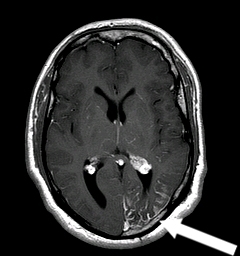

Sturge Weber

Sturge-Weber syndrome

Pathophysiology

Mutation in GNAQ gene

Clinical features

Port wine stain (trigeminal nerve [CN V1/V2] distribution) Leptomeningeal capillary-venous malformation Seizures ± hemiparesisIntellectual disability Visual field defects Glaucoma

Diagnosis

MRI of the brain with contrast

Management

Laser therapy Antiepileptic drugs Intraocular pressure reduction

This patient has had a new-onset seizure with a facial port wine stain and neurologic deficits, findings concerning for Sturge-Weber syndrome (SWS). SWS is a neurocutaneous disorder characterized by a capillary malformation (nevus flammeus, also known as port wine stain) in the distribution of the first or second branches of the trigeminal nerve with an associated leptomeningeal capillary-venous malformation affecting the brain and eye.

Patients with SWS have variable intellectual disability, which may present as developmental delays in infancy and early childhood. Seizures begin in early childhood and often originate focally with subsequent generalization, as seen in this patient. Hemiparesis contralateral to the intracranial malformation may present at the time of seizure onset. Glaucoma is the most common intraocular abnormality, and involvement of the occipital lobe or optic tract can cause visual field defects. For example, homonymous hemianopia, a defect in the right or left visual field of both eyes, results from a lesion involving the contralateral visual pathway.

MRI of the brain with contrast detects the intracranial vascular malformation and is diagnostic. Treatment is aimed at controlling seizures and reducing intraocular pressure. Laser therapy is also helpful in reducing the appearance of the port wine stain.